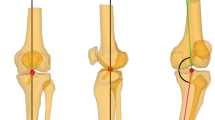

The mechanical lateral distal femoral articular angle (mLDFA) was defined as the lateral angle between the femoral mechanical axis and the distal femoral articular axis [16] (Fig. 1a). The medial proximal tibial angle (MPTA) was unique among the measurements in that it was included in both the mechanical parameters and the anatomical parameters and was defined as the medial angle between the mechanical (as well as anatomical) axis of the tibia and the proximal tibial articular axis (Fig. 1b). The mechanical tibiofemoral angle (mTFA) [16] was defined as the angle between the femoral mechanical axis and the tibial mechanical axis with a positive value indicative of a valgus alignment and a negative value indicative of a varus alignment of the lower extremity (Fig. 1c). The joint line convergence angle (JLCA) was defined as the angle between the proximal tibial and distal femoral articular axes with a negative value indicative of convergence laterally and a positive value indicative of convergence medially (Fig. 1d).

Anatomical angle measurements

The anatomic tibiofemoral angle (aTFA) [16] was defined as the angle between the anatomical axis of the femur and the anatomical-mechanical axis of the tibia (Fig. 1e). Once again, a positive value was indicative of a valgus and a negative value indicative of a varus alignment of the lower extremity. The angle between the mechanical and anatomical axes of the femur was defined as the anatomical-mechanical angle (AMA) [16] (Fig. 1f). The anatomical lateral distal femoral angle (aLDFA) was defined as the angle between the anatomical axis of the femur and the distal femoral articular axis [16] (Fig. 1g).

The anatomical medial proximal tibial angle was by convention defined to be equivalent to the medial proximal tibial angle (MPTA) due to the equivalence of the mechanical and anatomical tibial axes as noted above.